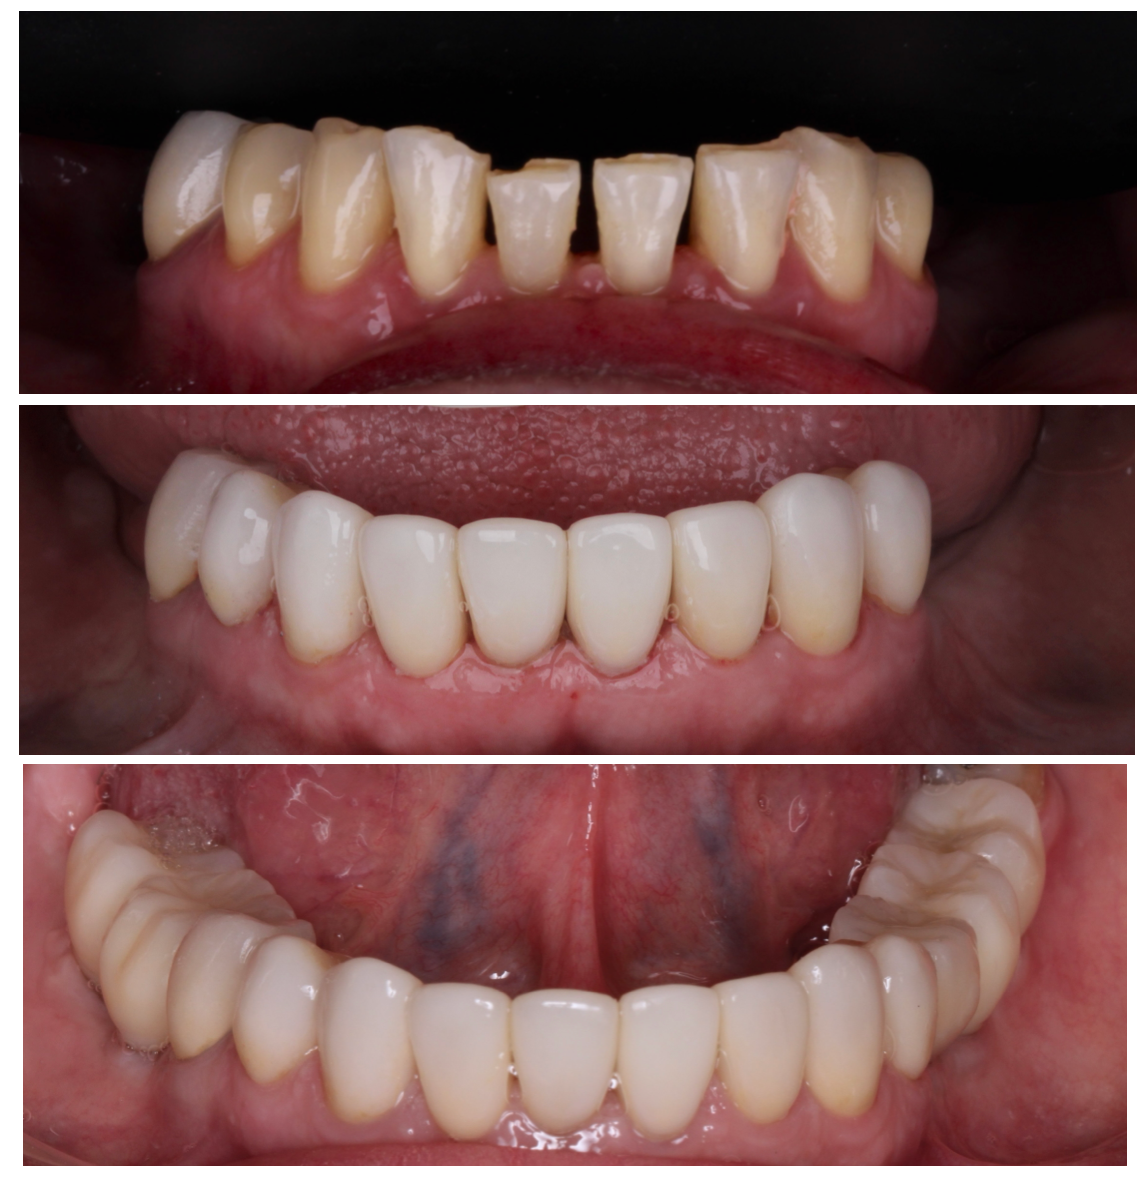

“La prótesis adecuada transforma mucho más que una sonrisa: mejora tu vida.”

Soy Gabriela González, especialista en prostodoncia comprometida con restaurar la función, estética y confianza de cada paciente.

Mi objetivo es ofrecer tratamientos personalizados que se adapten a tus necesidades, combinando técnicas tradicionales con tecnología moderna para lograr resultados naturales, cómodos y eficientes.

Cada caso representa una nueva oportunidad de ayudarte a volver a comer, hablar y sonreír sin limitaciones, con la seguridad y bienestar que mereces.

Diseño de sonrisa

Armonización estética con enfoque funcional.